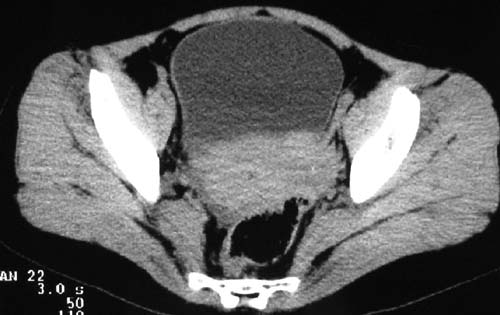

二、男,55岁,排尿困难两年,b超示盆腔不均质包块,ct值约27hu.

第二例可能为脐尿管肿瘤。

例2:盆腔占位,肿块密度欠均匀,其内有钙化影,其边界清晰,膀胱前上壁受压,膀胱壁尚清晰,考虑为不典型畸胎瘤压迫膀胱可能,建议增强扫描吧。

病例1;畸胎瘤,子宫肌瘤。病例2,与膀胱关系密切,脐尿管癌?

1.盆腔畸胎瘤

2.考虑脐尿管肿瘤

1典型盆腔畸胎瘤.2考虑脐尿管类肿瘤,建议增强扫描.

病例1,盆腔畸胎瘤并子宫肌瘤;病例2,囊性肿块,周围有壳状钙化,膀胱受压改变,考虑:脐尿管囊肿并感染,畸胎瘤?

1盆腔畸胎瘤伴子宫肌瘤2 第二例可能为脐尿管肿瘤。